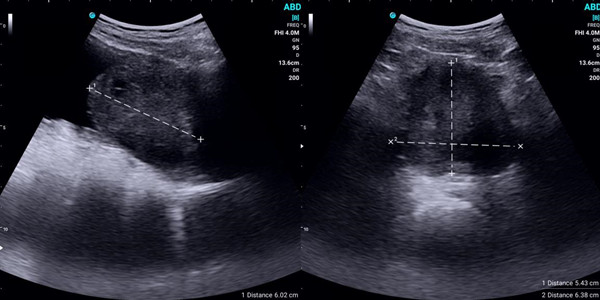

Reduced Need for Additional Tests

By providing clear and immediate images, handheld ultrasounds can often eliminate the need for further, more invasive tests. This not only speeds up the diagnostic process but also reduces patient anxiety and discomfort associated with additional procedures.

Real-Time Visualization

Healthcare providers can use handheld ultrasound devices to show patients real-time images of their internal organs and structures. This visual aid helps patients understand their conditions better and appreciate the diagnostic process. Improved understanding often leads to increased trust and confidence in the care they receive.